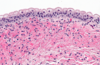

What are the KEY features on this H and E taken from a kidney tumor? Tumor Type?

•uniform round cells with abundant, intensely eosinophilic and granular cytoplasm = MITOCHONDRIA

***NOTABLY no PLEOMORPHISM***

•uniform small, round and central nuclei, Evenly dispersed chromatin

What is shown here?

• key features?

Oncocytoma

Key Features:

- Oncocytic = pink and grainy with sheets of pink and grainy PINK cells

- UNIFORM, not much pleomorphism

- smooth cell borders